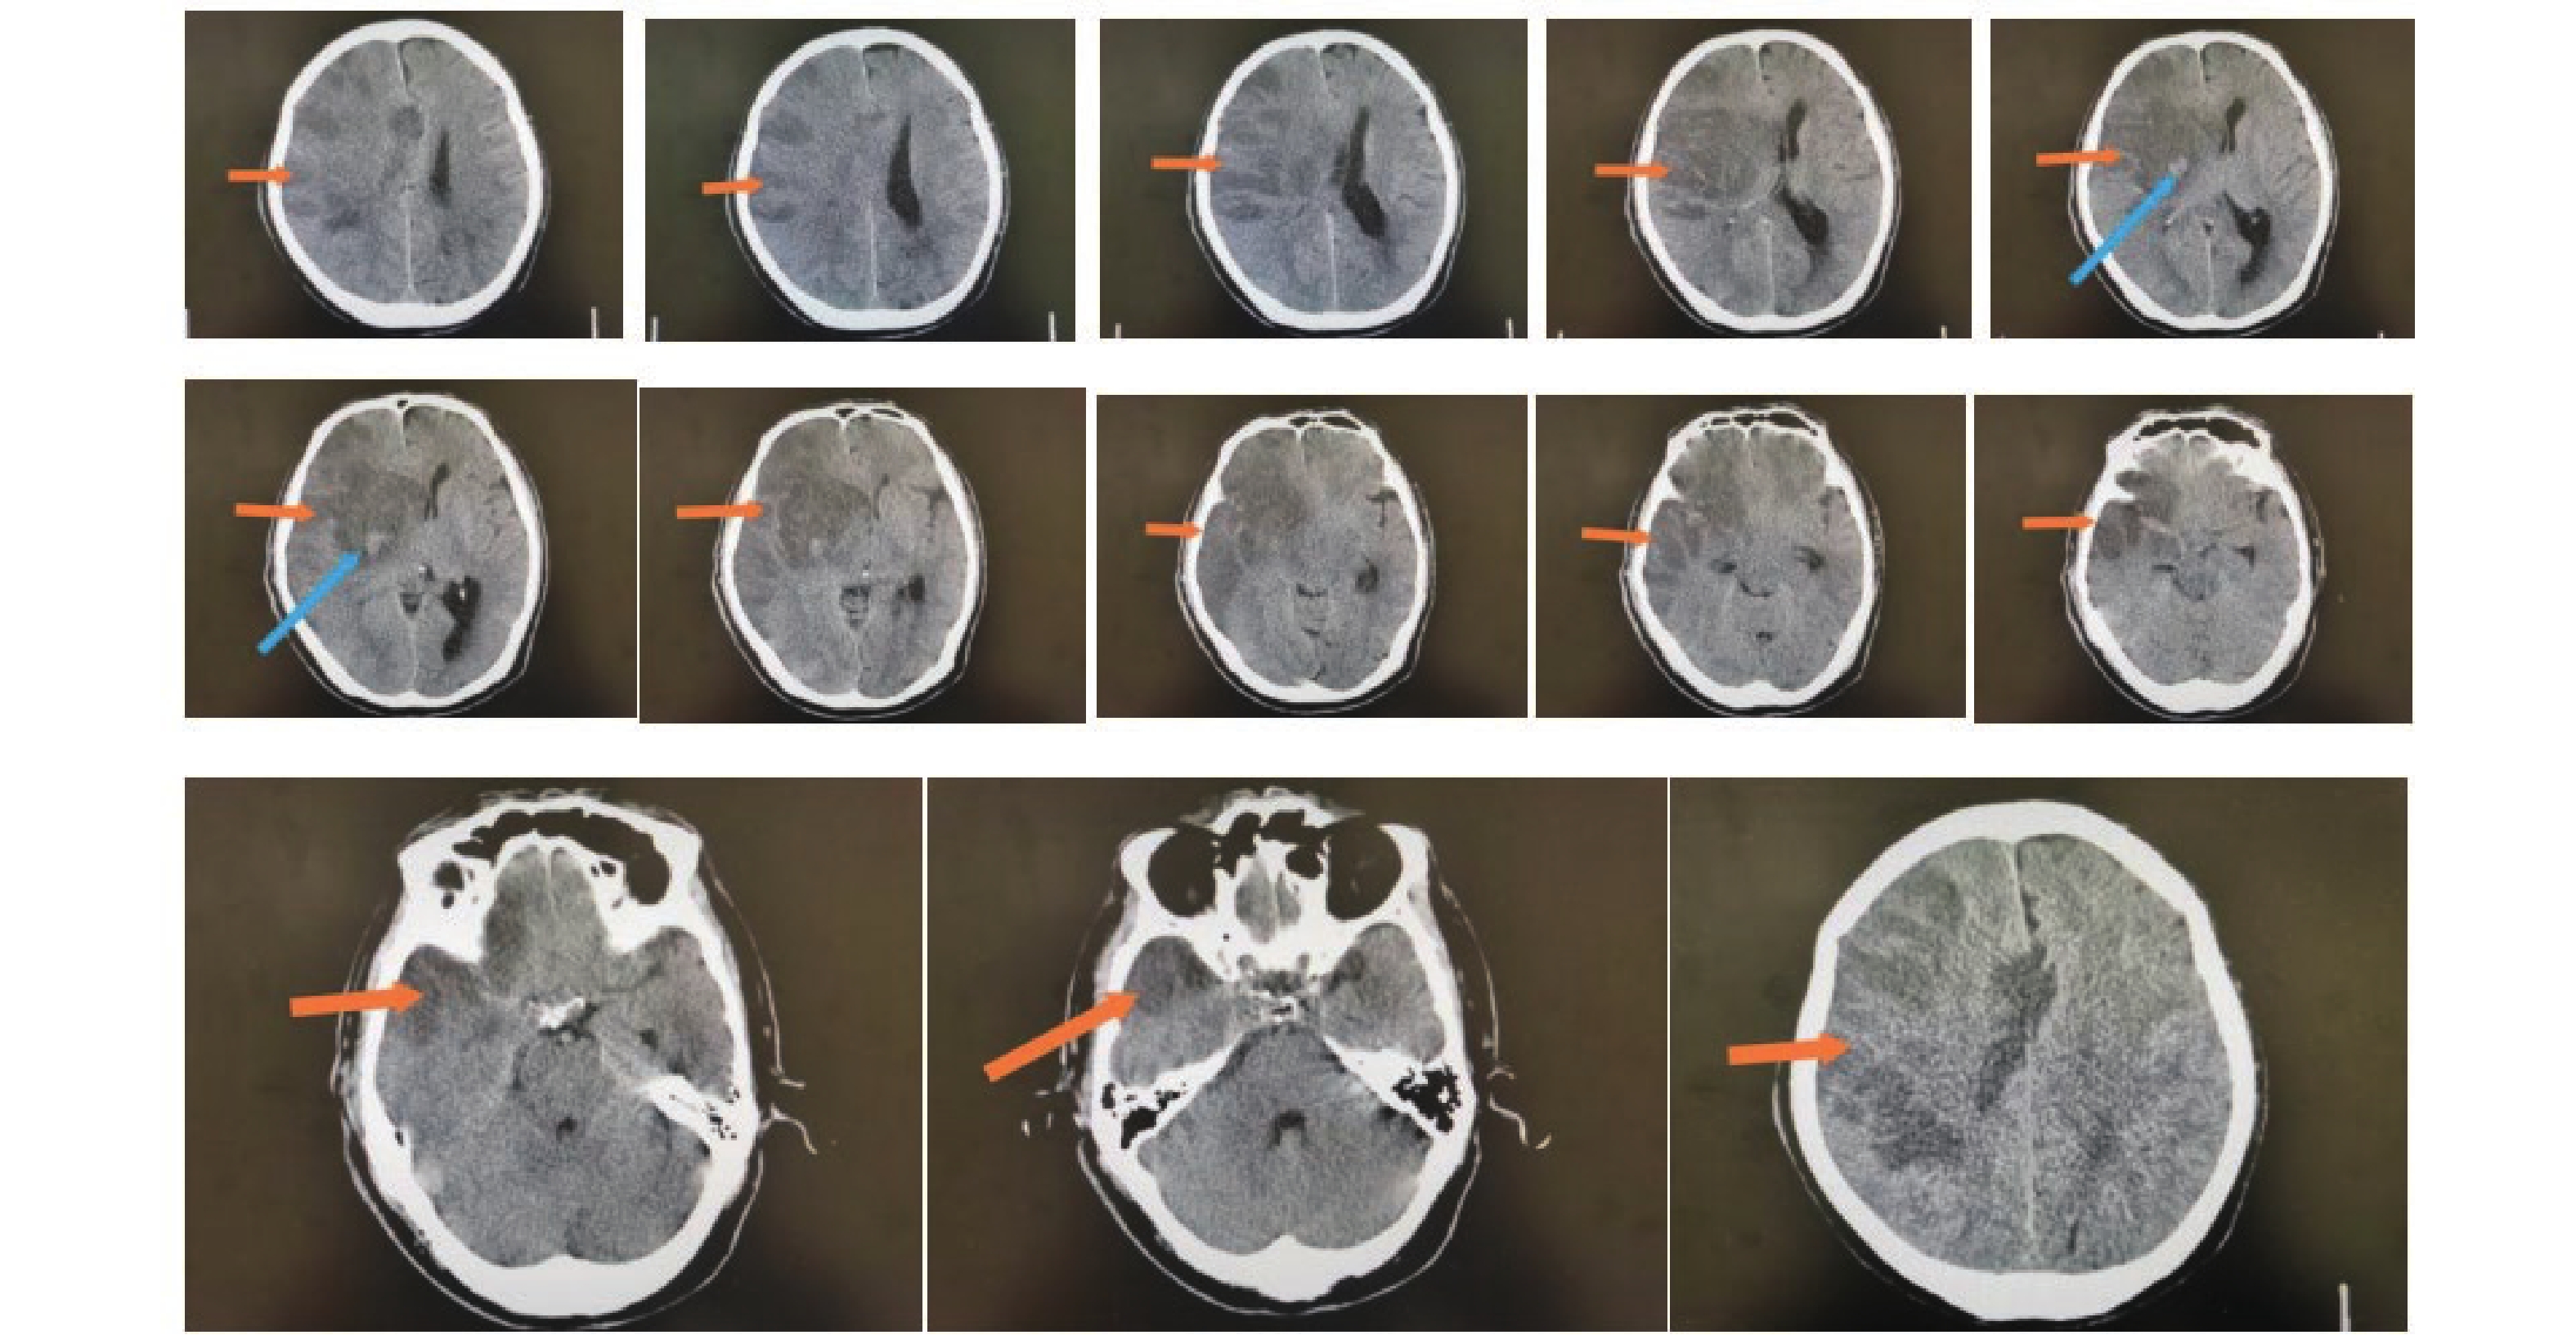

• 图  1  不良组术前头颅影像学表现

注:男性患者,67岁,从CT上看右侧额叶、颞叶、顶叶、岛叶大面积脑梗塞伴出血,中线左移,脑疝形成。其中橙色箭头指向低密度区为梗塞区,蓝色箭头指向较高密度区为出血。

Figure  1.  Preoperative cranial imaging findings in the poor outcome group